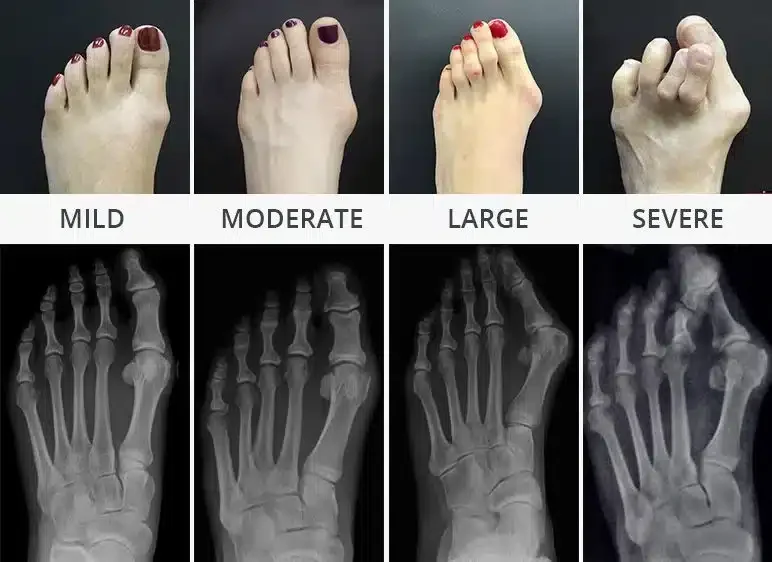

A bunion is a progressive structural deformity of the first joint at the base of the big toe. Often characterized by a visible bony protrusion on the inner side of the foot, a bunion occurs when the big toe (hallux) begins to lean inward toward the second toe. This shift forces the metatarsal bone to protrude outward, creating a misalignment that can make walking painful and finding comfortable footwear a significant challenge.

While many believe a bunion is simply an overgrowth of bone, it is actually a complex change in foot framework. The condition starts with a displacement between the first metatarsal bone and the big toe bone. As these bones shift out of alignment, the joint becomes prominent and the surrounding skin often becomes inflamed due to friction against footwear. Internally, a fluid-filled sac called a bursa cushions the joint; as the bunion progresses, this bursa can become thickened and inflamed (bursitis), leading to increased swelling and a deep, throbbing ache within the joint.

• Shifted Alignment: In advanced cases, the big toe may overlap or dive under the second toe, leading to secondary issues like hammertoes.